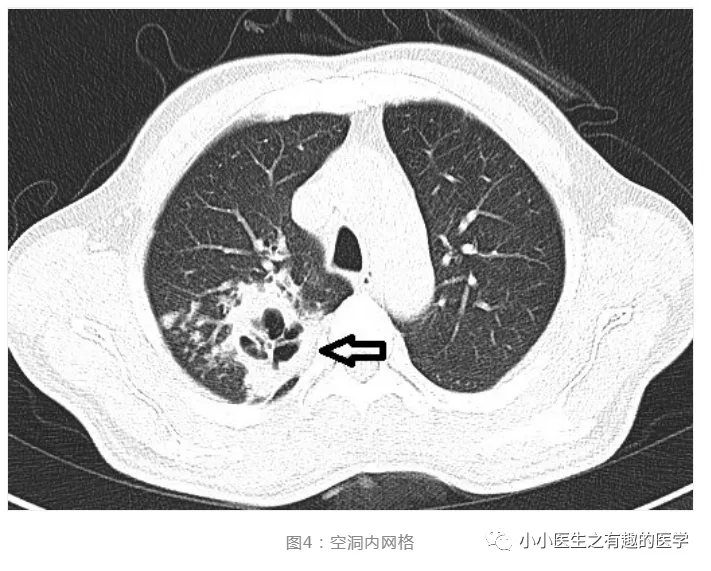

肺空洞血管穿行征或大有用处

图片尺寸711x571